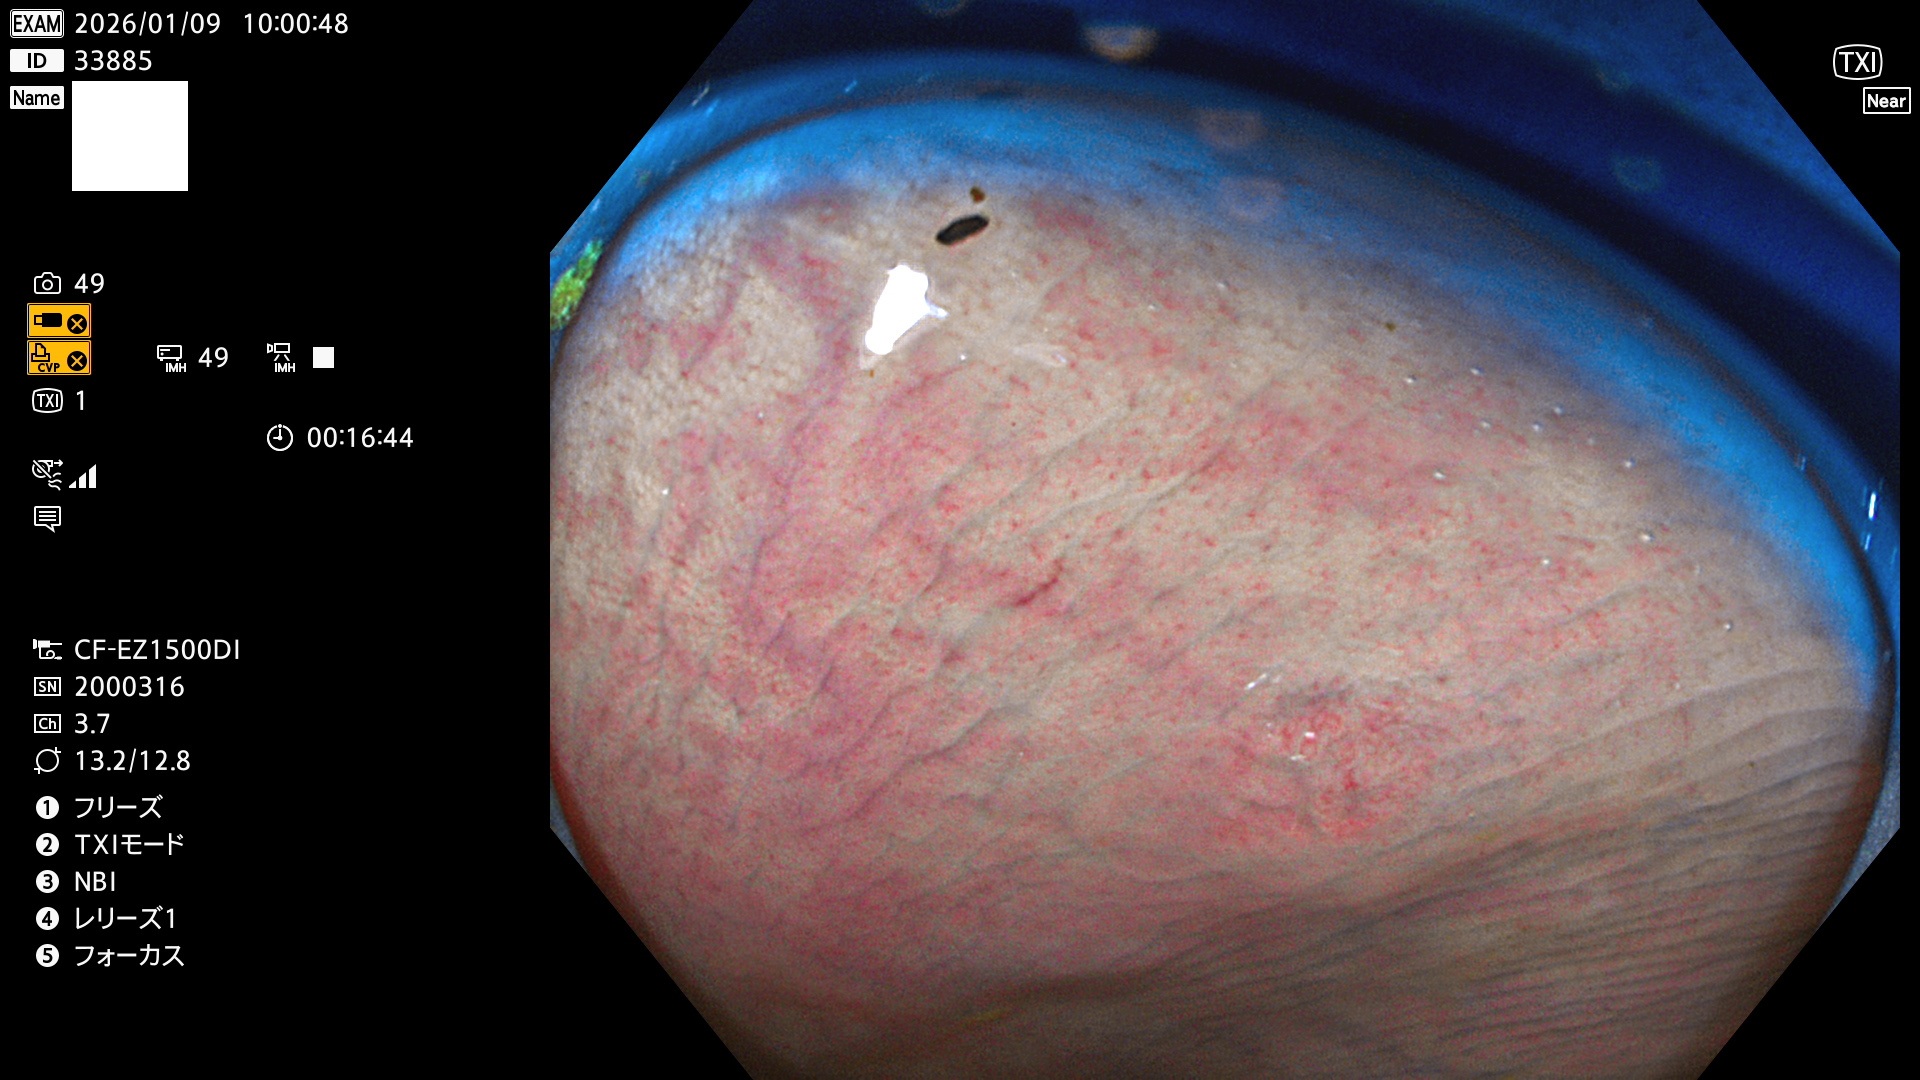

完全に平坦な物をUb、陥凹している物をUcと呼びます。Ubは認識が困難で、Ucはびらん(炎症)と紛らわしいために見落とされやすく、「内視鏡後・大腸癌」の原因になります。

専門的)Uc=De Novo癌? 内視鏡の解像度が低かった時代、このような説もありました。しかし今日の高精度内視鏡では良性の微小なUc型腺腫(APC遺伝子異常の腺腫)が日常的に見つかります。Ucこそが多段階発癌(Adenoma-Carcinoma Sequence)のMain Routeです。

毎週の検査(木・金・土・日)に発見されたUbとUc型・腺腫を、その週の日曜の夜にUPし1週間、提示します。

2026年1月8日〜1月11日の4日間(40件)6個 (Uc_ADR=6個/40人=15%)